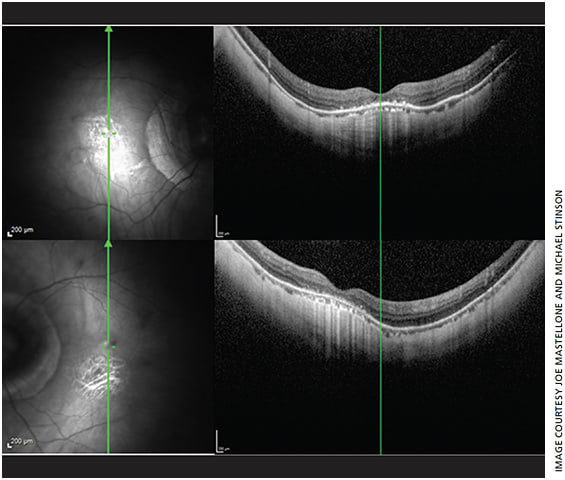

- OCT of the macula revealed multiple degenerative changes consistent with pathologic myopia (Figure 3). OCT of the optic nerve was not able to be interpreted due to the extent of the scleral crescent.

Figure 3. SD-OCT images of the right (top) and left (bottom) maculae exhibiting dome-shaped configuration adjacent to posterior staphyloma and peripapillary atrophy. Presence of choroidal thinning, outer segment atrophy, mild RPE atrophy and foveal exudates are consistent with diagnosis of pathologic myopia. Image taken with a Heidelberg Spectralis. - Given combination of a subluxated IOL and myopic stigmata in the posterior segment, we diagnosed our patient with spontaneous IOL subluxation OD secondary to zonular insufficiency from pathologic myopia.